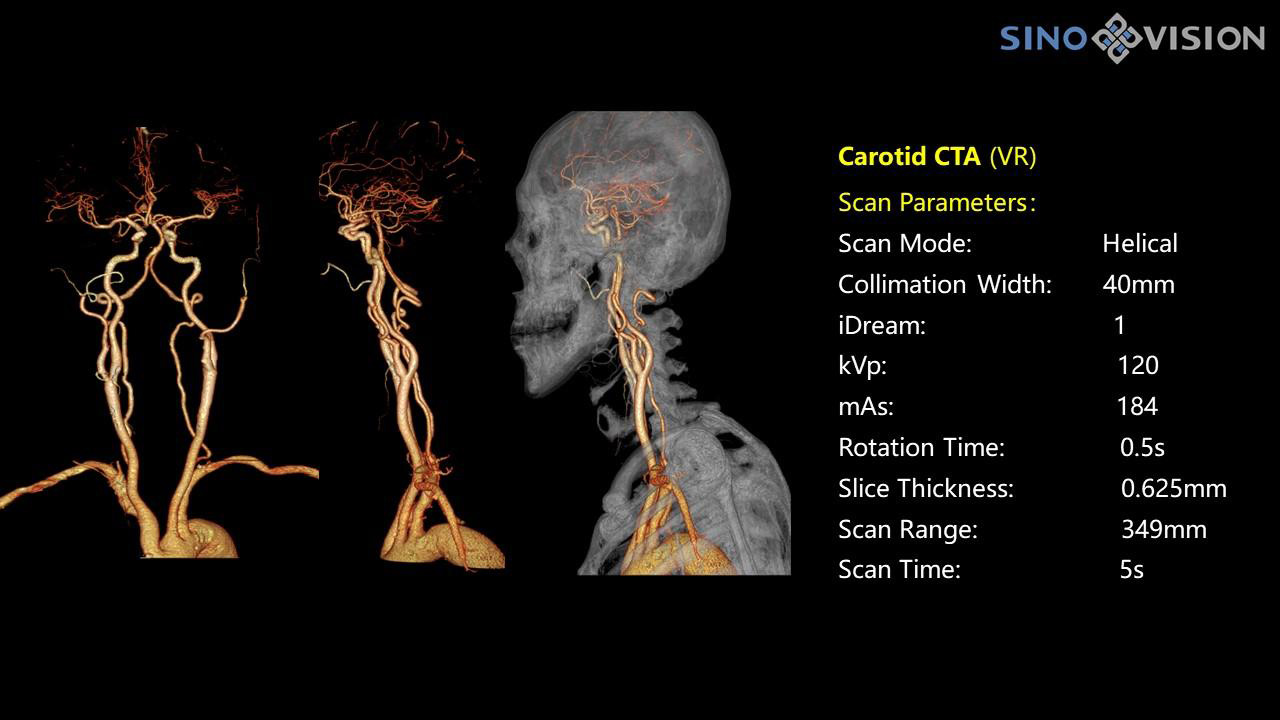

InsitumCT 768 является вершиной нового поколения широкоапертурных широкополосных компьютерных томографов. Этот КТ-сканер обеспечивает 128 срезов КТ при апертуре 76 см, увеличивая производительность визуализации до 21 л/см, способствуя точной диагностике и лечению заболеваний и значительно улучшая клинические характеристики и масштабируемость. Обеспечивает получение изображений высокого разрешения при низкой дозе облучения.

Компьютерный томограф Insitum CT 768 – старшая модель в линейке SinoVision Insitum. Еще более быстрый и еще более мощный, он значительно повышает пропускную способность кабинета КТ, обеспечивая при этом высококачественные исследования даже в самых сложных случаях практически во всех областях, включая кардиологию, исследования сосудистой системы, онкологию. Имеет специализированный педиатрический протокол исследования, минимализирующий лучевую нагрузку на ребенка.

Специализированная технология RTF позволяет уменьшать артефакты движения сердца, обеспечивая максимально точное клиническое изображение.

- Количество срезов: 128

- Толщина среза: 0.625 мм

Характеристики сканирования

- Минимальное время одного оборота рентгеновской трубки: От 0.37 до 2 сек

- Коронарный анализ

- Общий анализа сосудов на основе серии данных КТ

- Ретроспективный режим сканирования с ЭКГ-синхронизацией

- Проспективный режим сканирования с ЭКГ-синхронизацией

- Режим последовательного сканирования c ЭКГ-синхронизацией и без ЭКГ-синхронизации